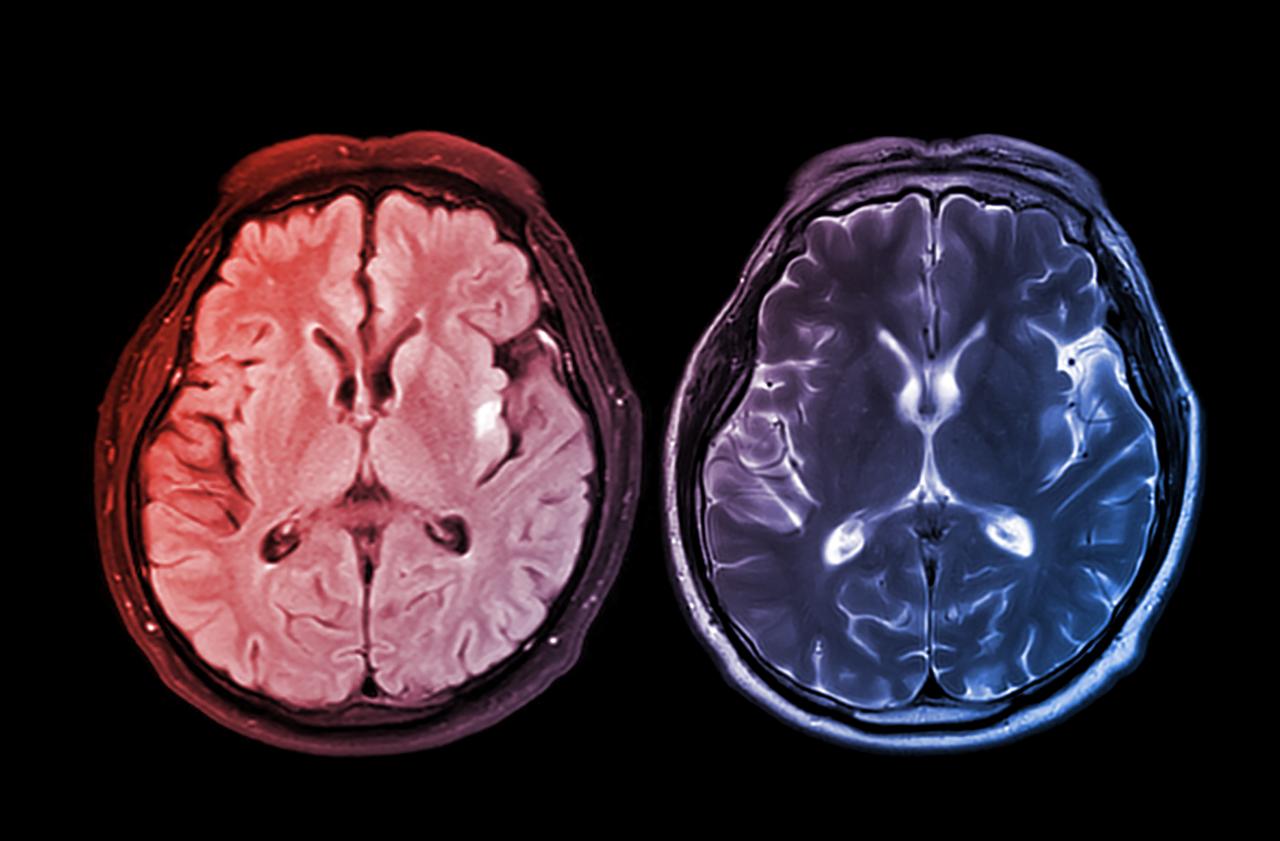

A járvány hosszú távú hatása nemcsak azokat érinthette, akik elkapták a COVID–19-et. Egy friss brit tanulmány szerint már pusztán a világjárvány miatti stressz, bizonytalanság és izoláció is érezhető nyomot hagyott az agyban.

Kutatók közel ezer egészséges felnőtt MRI-felvételeit elemezték a COVID–19 előtt és alatt. Átlagosan öt és fél hónappal öregebbnek tűntek a résztvevők agyai annál, mint amit a pandémia előtti trendek alapján várni lehetett volna. Egy MI-alapú modell segítségével több száz agyi struktúrát vizsgáltak, és az azonosított elváltozások még azoknál is kimutathatók voltak, akik sosem kapták el a vírust.

Bár az MRI-eredmények szerint gyorsabbá vált az agy öregedése, a feldolgozási sebesség és a problémamegoldó képesség nem mindenkinél gyengült észrevehetően. A szerkezeti változások tehát nem azonnal vezetnek kognitív hanyatláshoz.

A kutatók szerint maga a fertőzés is okozhat tartós agyi elváltozásokat, ám legalább ilyen fontos tényező lehet a járványhelyzet okozta stressz, magány és gyász is. Ezek mind hozzájárulhatnak az agy változásaihoz.